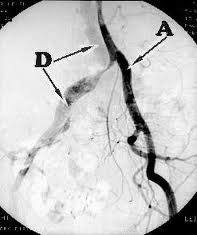

Femoro Popliteal Bypass using Vein Graft

Supra-Celiac Aorto Femoral Bypass

Popliteo-Distal Bypass